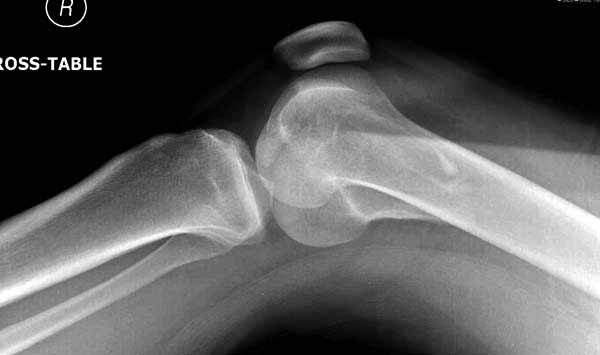

И не обратите, коллега, пока не сделаете четкие анфасные снимки (лучше с дистракцией) где будет четко визуализироваться малоберцовая кость. Думается, что и КТ здесь будет уместно, дабы не пропустить возможное флексионное повреждение (перелом Hoffa).

А теперь по поводу лечения перелома. Среди всех чрез/меж-мыщелковых переломов в 38% сопровождются переломом в корональной плоскости, т.е перелом Hoffa. Nork et al, J Orthop Trauma, 87:564, 2005.

Однако в случае, представленном Константином Никитиным, не может быть применён ни ретроградный ни антеградный остеосинтез. Причина - нереально выполнить вышеуказанные необходимые требования, касающиеся дистальных блокирующих винтов. Из-за низкого перелома латерального мыщелка (перелом Hoffa) невозможно через него провести хотя бы 2 блокирующих винта, поскольку линия перелома мыщелка расположена либо на уровне верхушки межмыщелковой ямки либо незначительно проксимальнее. Поэтому авторам, с моей точки зрения, необходимо прислушаться к рекомендациям Джолдаса.